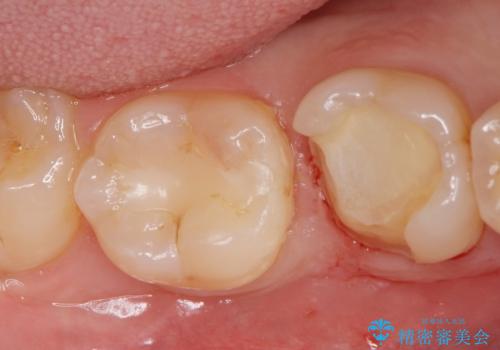

詰め物が欠けてしみる

- 過去に他院で治療した詰め物が欠けてしみるとの事で来院。

プラスチックの樹脂での治療(保険)でされており虫歯が再発していました。

あまり歯質を削って欲しくないとの事だったのでゴールドインレーでの治療になりました。